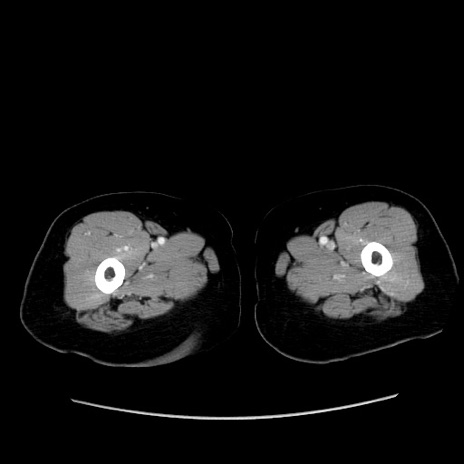

症例19(横断像)

【症例】80歳代女性

【主訴】下腹部痛

【現病歴】約8時間前より下腹部痛の出現あり、救急外来受診。

【既往歴】両側付属器切除

【身体所見】意識清明、下腹部正中に手術痕あり、その部位に一致して圧痛と反跳痛あり。腸蠕動音は亢進。

【データ】WBC 9300、CRP 0.15